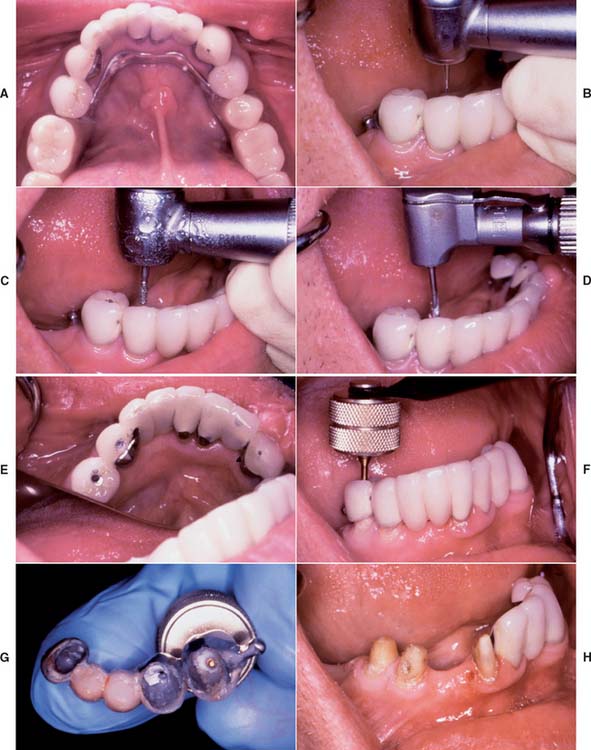

Fig. 32-21 The Metalift Crown and Bridge Removal System (Classic Practice Resources, Baton Rouge, Louisiana). A, Five-unit partial fixed dental prosthesis (FDP) supporting a partial removable dental prosthesis. The anterior abutment (right mandibular central incisor) is loose; the posterior abutments (both right mandibular premolars) are firmly cemented. B, Access to the metal on each abutment is provided by preparing through the porcelain with a diamond. C, The metal is penetrated with a No. 1 round bur to create a pilot channel in each abutment. D, The pilot hole is followed by the special drill. E, The holes should just penetrate the metal, as indicated by the visible cement. F, The Metalift instrument is threaded into both crowns, breaking the cement seal. G, The partial FDP is removed, and if the abutments are satisfactory as seen here (H), it can be recemented for further service. The manufacturer supplies threaded keys that can be used to seal the occlusal holes. To facilitate recovery, they can also be incorporated in crowns before cementation.

(Courtesy of Dr. R. D. Westerman.)